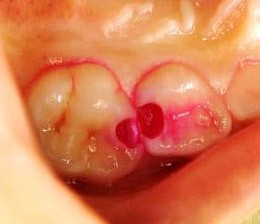

神経が露出している場合は「直接覆髄法」

虫歯が進行すると、削った際に神経が露出してしまうことがあります。

神経は細菌に弱く、感染すると炎症を起こしやすくなるため、治療では細菌の侵入や炎症を防ぐことが最も重要です。

このような場合に行うのが、「直接覆髄法」です。

露出した神経の上を、「MTAセメント」で直接覆い、殺菌と保護を行います。

神経を守りながら、できるだけ歯を残すための治療法です。

部分的な炎症は「断髄法」で治療

虫歯が深く進行し、神経に達している場合、神経を取る治療を提案されることが多くあります。

ただし、炎症が神経の一部に限られているときは、すべての神経を除去する必要はありません。

そのようなケースでは、部分断髄法を選択します。

部分断髄法では、炎症を起こしている神経だけを取り除き、健康な神経はできるだけ残します。

切除した部分はMTAセメントやバイオセラミックで覆い、神経を保護します。

歯の機能を保ちながら、神経を残すための治療法です。